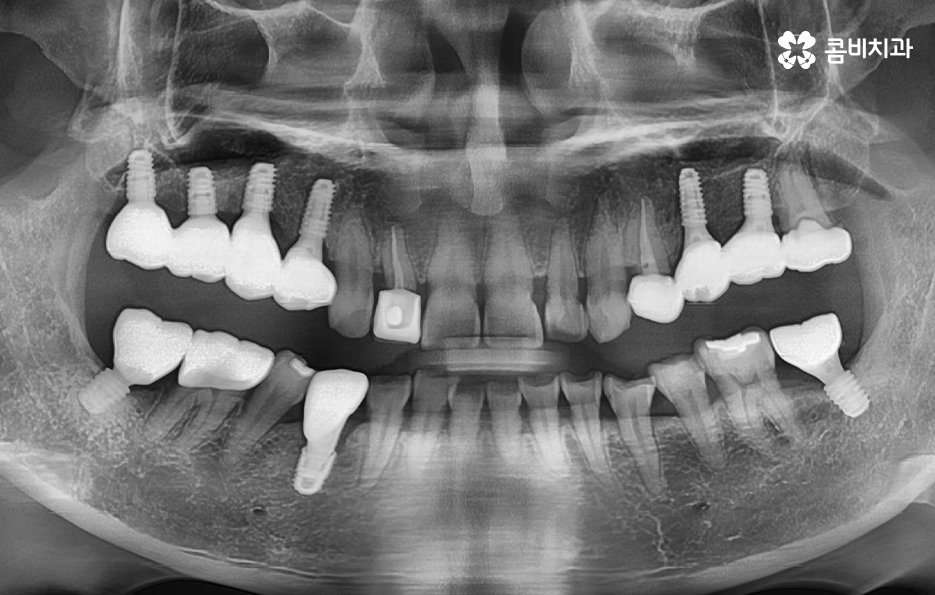

우리가 보편적으로 생각하게 되는 임플란트 치료기간의 경우 치아 하나를 상실하고 임플란트를 1:1로 치료할 때 예상 기간에 대해서 고려하게 되는 경우가 기본적인 접근 방법이라면 실질적으로 치과에서 임플란트를 하게 되는 연령대를 보더라도 보통 50대에서 60대 이후에 치아를 상실하게 되는 환자분들이 급증하기 때문에 위 사진의 사례처럼 여러 치아를 상실하고 임플란트를 식립하게 되는 경우도 많을 거예요